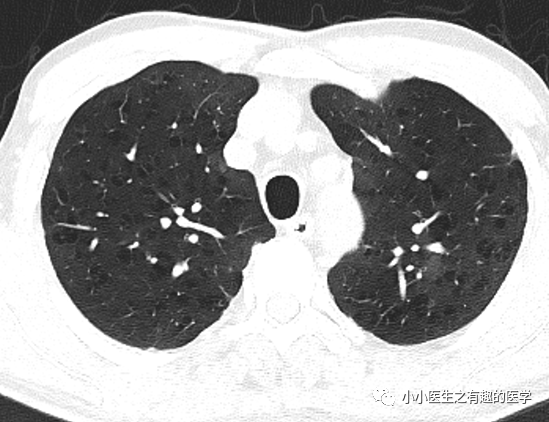

ct研习社肺气肿的分类

和下部的横轴位ct,显示肺上叶少数较小的小叶中央型和间隔旁型肺气肿